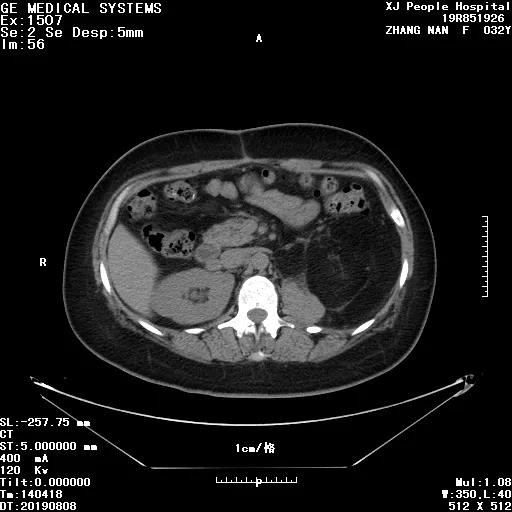

腹部增强 CT: 腹腔腹膜后及盆腔内巨大脂肪密度为混杂密度占位,左侧肾上腺正常结构显示不清,病变包饶左肾,临近脏器、组织受压、推移、脂肪肉瘤?血管平滑肌脂肪瘤?请结合临床(图 1)。

图 1:入院腹部增强 CT